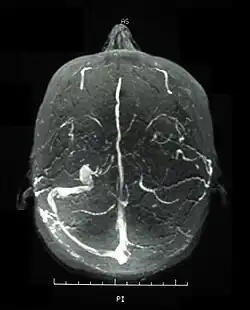

Inflammatory eye disease can develop early in the disease course and lead to permanent vision loss in 20 percent of cases. Ocular involvement can be in the form of posterior uveitis, anterior uveitis, or retinal vasculitis. Anterior uveitis presents with painful eyes, conjuctival redness, hypopyon, and decreased visual acuity, while posterior uveitis presents with painless decreased visual acuity and visual field floaters. A rare form of ocular (eye) involvement in this syndrome is retinal vasculitis which presents with painless decrease of vision with the possibility of floaters or visual field defects.[4]